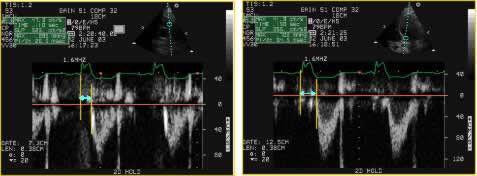

Figure 2

Interventricular asynchrony is assessed with PW - Doppler applied at the aortic and pulmonary valves measuring the difference between the aortic pre-ejection time and the pulmonary pre-ejection time defined as the time passed from the beginning of the QRS complex to the beginning of the pulmonary or aortic ejection.

Interventricular asynchrony refers to the decoordination between right and LV contraction. Physiologically LV contraction occurs 10 to 20 ms later than the right ventricle; when this time difference is superior to 40 ms, this indicates interventricular asynchrony.

This delay between the contractions of both ventricles can also be measured with echo by calculating the time difference between both, pulmonary and aortic pre-ejective times, which are again obtained with PW - Doppler applied on the pulmonary and aortic valves as it is shown in Figure 2.